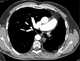

Hypoplastic contralateral pulmonary artery

Unilateral hilar enlargement